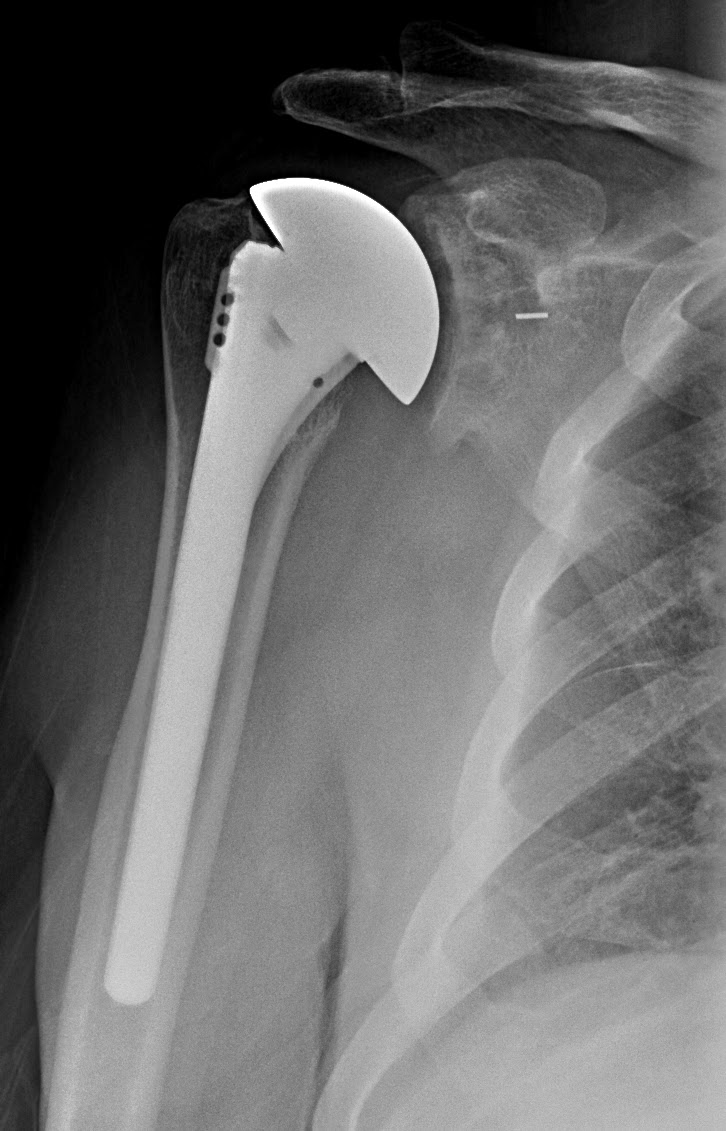

UW Shoulder and Elbow Academy Cuff tear arthropathy the use of a CTA Shoulder Pain Arthritis Or Rotator Cuff Injuries to the rotator cuff are common and can lead to a form of shoulder arthritis called rotator cuff tear arthropathy. In the shoulder, arthritis causes pain and stiffness that can make it difficult to lift your arm, brush your hair, reach up to a high shelf, or perform. Pain from a problem with the rotator cuff is often called. Shoulder Pain Arthritis Or Rotator Cuff.